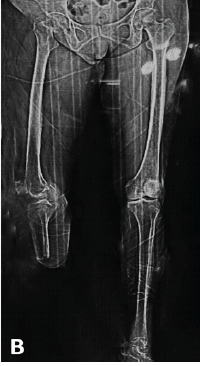

A Rare and Interesting Case of Sciatic Nerve Compression Due to Proximal Femoral Osteochondroma in a Young Adult – A Case Report

Ninad Kishor Honwadkar , Eknath Deosing Pawar , Abhiram T V , Aravind Chanal , Atharva Alaspure